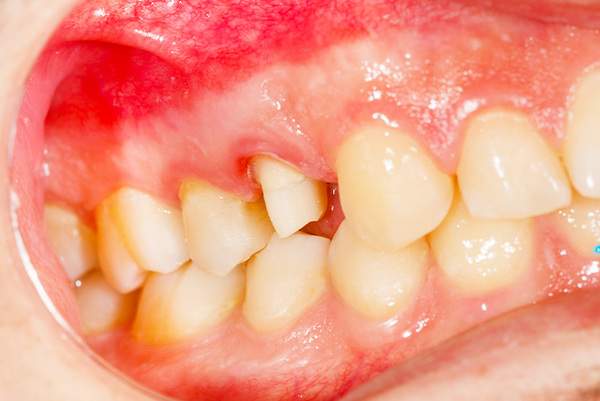

妊娠性歯肉炎

妊娠してから歯ブラシの時に歯茎から出血するようになった、歯茎が腫れぼったいと感じている方は妊娠性歯肉炎かもしれません。

治療

歯肉炎の基本治療は、ブラッシング指導・歯石除去・お口の中の修復物のチェック・かみ合わせのチェック

です。

安定期にはいってからの本格的な治療をおすすめしているので、妊娠初期に出血や歯茎の腫れ・お痛みなど気になることがある場合は応急処置を行っていき、安定期にはいってから本格的な治療を行っていきます。

また、妊娠後期になりお腹が大きくなると治療体勢で苦しくなることがあるので積極的な治療は控えることをおすすめしています。